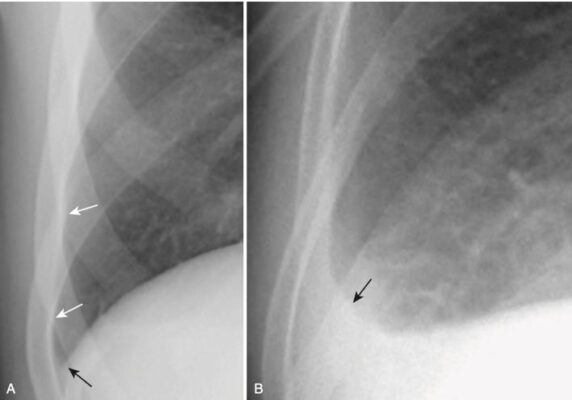

- Hầu hết các tràn dịch màng phổi đầu tiên tập trung ở một vị trí bên dưới phổi giữa màng phổi thành lót bề mặt trên của cơ hoành và màng phổi tạng dưới thùy dưới.

- Nếu tình trạng tràn dịch vẫn hoàn toàn ở dưới phổi, có thể khó phát hiện trên phim chụp X quang thông thường, ngoại trừ những thay đổi đường viền ở nơi dường như là cơ hoành nhưng trên thực tế là ở giao tiếp dịch – phổi bên dưới phổi.

- Các hình thức xuất hiện khác nhau của tràn dịch dưới phổi được tóm tắt trong Bảng 2 (Hình 2 và Hình 3).

- Dưới phổi không có nghĩa là khu trú.

- Hầu hết các tràn dịch dưới phổi di chuyển tự do khi bệnh nhân thay đổi tư thế.

BẢNG 2 NHẬN BIẾT MỘT TRÀN DỊCH DƯỚI PHỔI

.